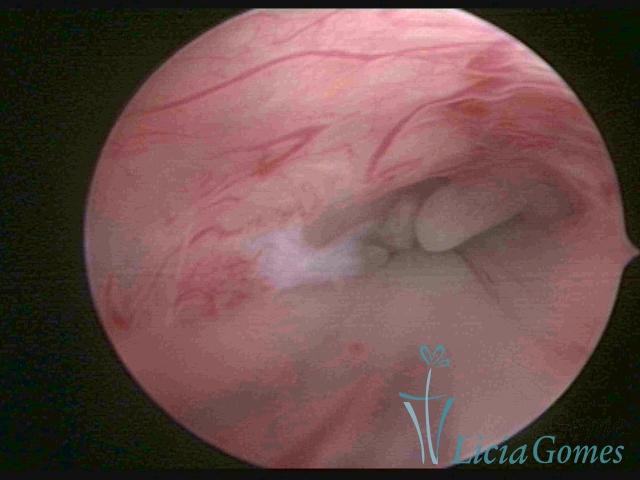

ENDOCERVICAL POLYPS

Benign tumors resulting from the reactive focal proliferation to inflammatory processes or hyperestrogenism situations, which may be sessile (with a large implantation) or stalked.